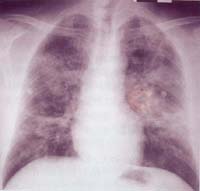

胸部X線

表現常呈多樣性,肺葉或肺大葉實變,好發於右肺上葉、雙肺下葉,有多發性蜂窩狀肺膿腫、葉間隙下墜。